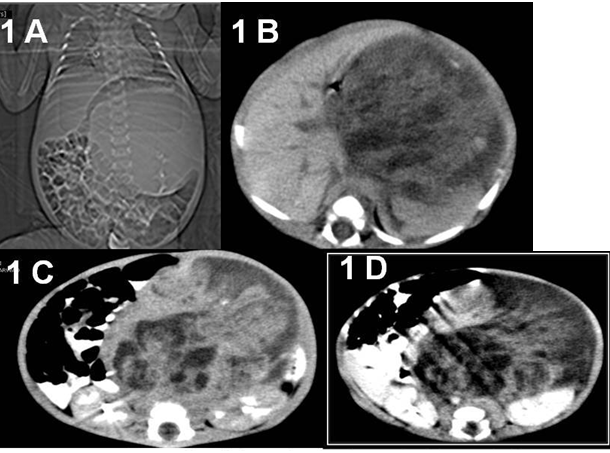

A 6 weeks old male infant, born by normal vaginal delivery at home, presented to our hospital with progressively increasing abdominal mass of 10 days duration, associated with poor feeding. Antenatal care was unsupervised. There was no history of fever, weight loss, bowel or urinary complaints. Post natal period was uneventful. On examination the abdomen was distended, a large firm mass occupying the central and left upper abdomen measuring about 15x 12x10 cm in maximum dimensions. No tenderness on palpation or overlying skin changes. The rest of general examination was unremarkable. Routine blood tests and urine analysis were all within normal limits. The serum levels of alpha-fetoprotein (AFP) was normal. A plain abdominal X-ray showed a well defined round radio-dense mass seen projecting at the left side of the abdomen, mass effect was evident marked displacement of the bowel loops peripherally (Figure 1A). Ultrasound of abdomen showed a large heterogeneous mass located on the left side associated with areas of cystic components. Contrast enhanced computed tomography (CECT) scan of the abdomen and pelvis demonstrates a large retroperitoneal heterogeneous mass occupying predominantly the left suprarenal region, measuring about 12 x 10 x 8 cm with two clumps of calcification, fatty tissue, and cystic contents. The mass crossing the midline was displacing the aorta and Inferior Vena Cava to the contralateral side and the left kidney posterior-inferiorly (Figure 1B&1C). The rest of abdominal and pelvic organs were within normal limits.

Figure 1 Images of computed tomography abdomen and pelvis.

1A CT topographic image showing large left sided abdominal mass displacing the bowel loops with internal calcification.

1B Plain CT axial image showing a large heterogeneous left suprarenal retroperitoneal mass with internal calcification.

1C Contrast CT axial image showing a large heterogeneously enhancing left suprarenal retroperitoneal mass with enhancing soft tissue components and non enhancing cystic and necrotic parts.

1D Contrast CT axial image showing a large heterogeneously enhancing left suprarenal retroperitoneal mass crossing midline, displacing aorta without encasing it. Left kidney is displaced inferiorly and compressed against the posterior abdominal wall.